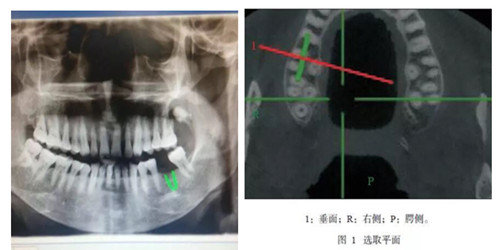

CBCT是一種錐形束投照計(jì)算機(jī)重組斷層影像設(shè)備,可用于種植、頜面外科、正畸、牙體牙髓病、牙周病等方面的檢查。通過(guò)口腔CT的立體影像可以全面了解頜骨形態(tài)、牙齒周圍的解剖結(jié)構(gòu),牙根的位置與形態(tài)、下頜神經(jīng)管的走向和范圍、上頜竇底的位置及上牙牙根與上頜竇的關(guān)系、下牙牙根與下頜神經(jīng)管的位置關(guān)系等肉眼不可見(jiàn)的組織結(jié)構(gòu)。

CBCT具有特點(diǎn):圖像分辨清晰、重建速度快速、重建時(shí)間低于15S,成像范圍合理、偽影校正技術(shù)獨(dú)特,避免重疊等,操作簡(jiǎn)單便捷,一次掃描即可獲得全口腔雙牙列三維立體影像 等一系列特點(diǎn)。與傳統(tǒng)CT相比CBCT的輻射量更低、牙齒與頜骨成像更加清晰。我院CBCT附送患者一張影像刻錄光盤,觀看膠片不需要觀片燈,直接在醫(yī)生電腦上即可動(dòng)態(tài)觀看圖像;消除患者等待煩惱。